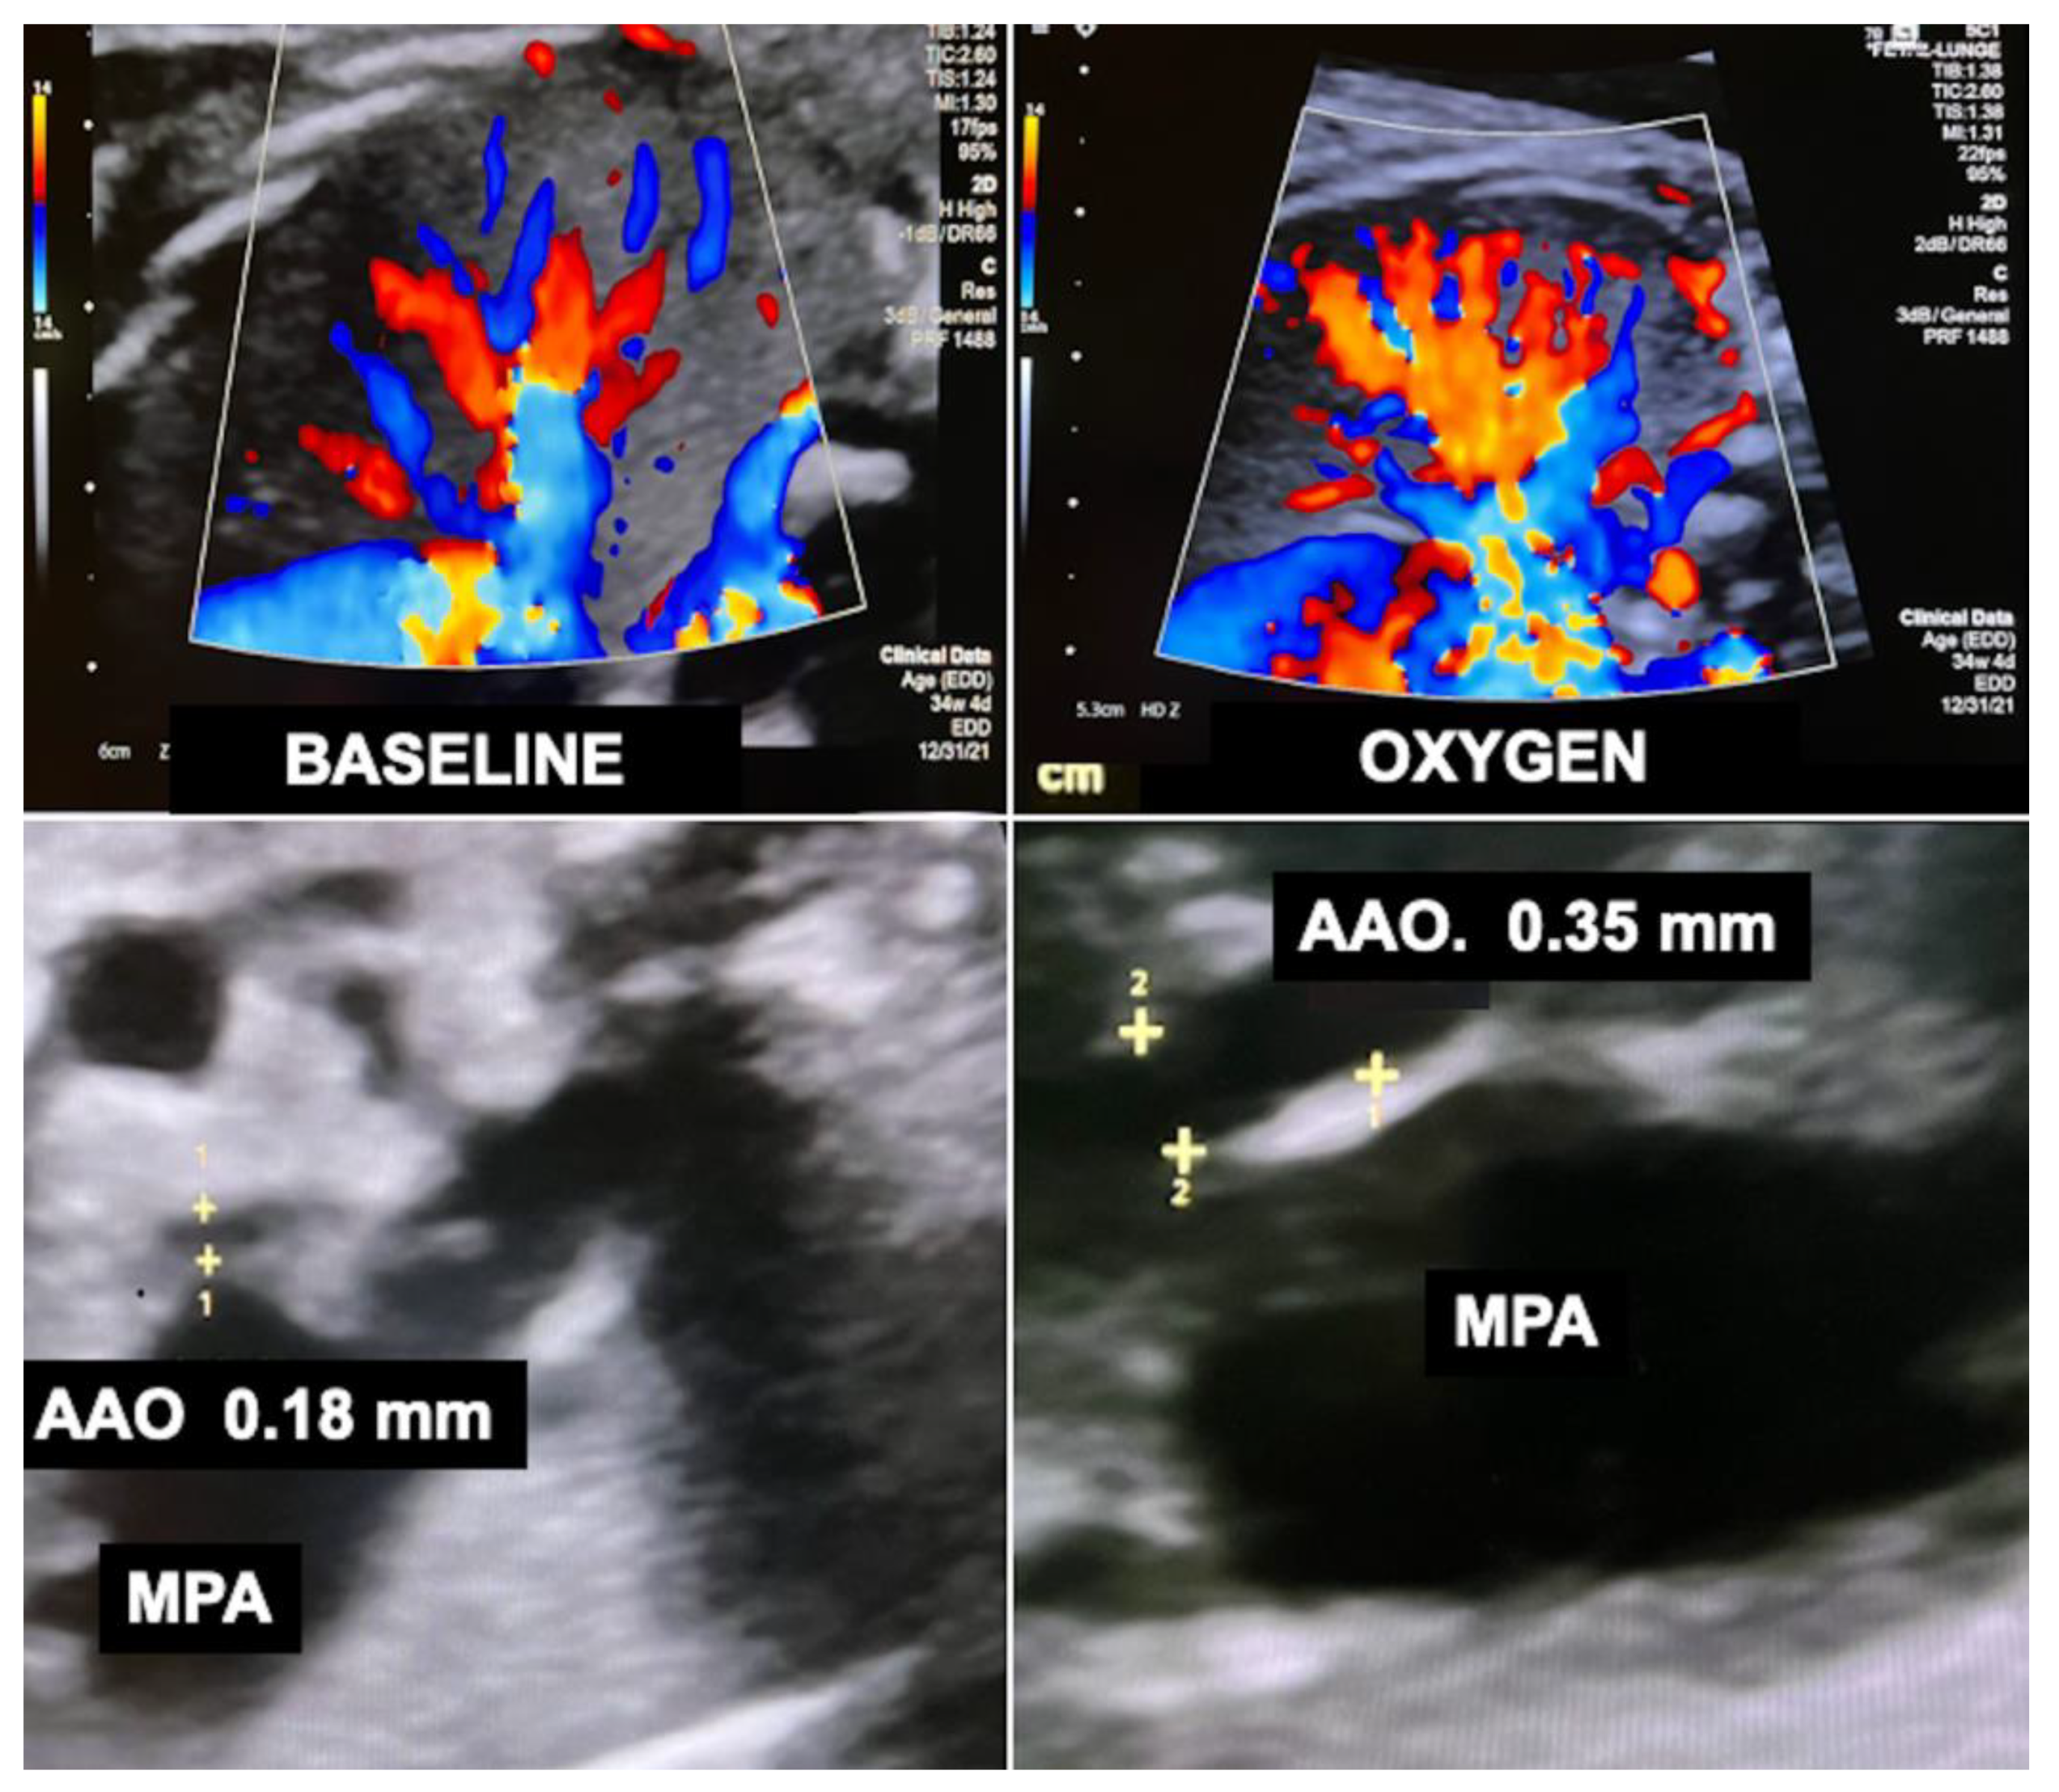

In order to overcome this limitation, additional hemodynamic studies of fetuses with diaphragmatic hernia—with a particular focus on fetal left–right-heart-symmetry—can be performed, such as assessment of ductus venosus streaming and lung blood flow monitoring [41,42,43]. Using these parameters, I have observed that most fetuses with liver-down left diaphragmatic hernia exhibit normal streaming of ductus venosus blood into the left side of the heart of the fetus. As a result, both sides of the heart are of equal size, pulmonary blood flow signals are easily visualized, and pulmonary vasodilation in response to diagnostic maternal hyperoxygenation can be produced (Figure 3). Taken together, these findings point to a milder postnatal treatment course and herald a better prognosis.

Figure 3.

Examples of lung blood flows of a normal fetus (top left) and fetuses with diaphragmatic hernia during diagnostic materno–fetal hyperoxygenation. Most fetuses with liver-down left diaphragmatic hernia (L-DH) exhibit normal streaming of ductus venosus blood into the left side of the heart (bottom left). As a result, both sides of the heart are of equal size, pulmonary blood flow signals are easily visualized, and pulmonary vasodilation in response to diagnostic maternal hyperoxygenation can be produced. In contrast, most fetuses with liver-up L-DH exhibit preferential streaming of ductus venosus blood into the right side of the heart of the fetus. As a result, there is less preload to the left side of the heart, which in turn becomes hypoplastic. In addition, pulmonary blood flow is often markedly decreased (bottom right). Fetuses with right diaphragmatic hernia (R-DH), despite liver herniation, present with normal ductus venosus streaming into the heart. Therefore, as a rule, in these fetuses, neither isolated left, nor isolated right heart hypoplasia are observed, and color Doppler signals of pulmonary blood flow are often normal (top right).

In contrast, most fetuses with liver-up left diaphragmatic hernia exhibit preferential streaming of ductus venosus blood into the right side of the heart of the fetus. As a result, there is less preload to the left side of the heart, which in turn becomes hypoplastic. Probably as a result of the oxygen-enriched ductus venous blood reaching the lungs, morphologic changes contributing to pulmonary hypertension can develop. During Doppler ultrasound studies, pulmonary blood flow signals are less pronounced and pulmonary vasodilation in response to materno–fetal hyperoxygenation is often markedly attenuated (Figure 3).

In contrast, fetuses with right diaphragmatic hernia—despite liver herniation—present with a more normal infracardiac spatial arrangement of venous vessels, and hence, normal distribution of ductus venosus blood within the fetal heart [43]. Therefore, as a rule, in these fetuses, neither isolated left, nor isolated right heart hypoplasia are observed (I have encountered only one exception) (Figure 3). Nevertheless, there may be symmetrical underdevelopment of both, left and right cardiovascular structures, from compression by the herniated organs. Yet even in severe cases, a close to normal degree of blood flow can be observed within the left lung (Figure 3). In ECMO centers such as ours, this hemodynamic advantage seems to contribute to survival rates of more than 80% for this condition [34].